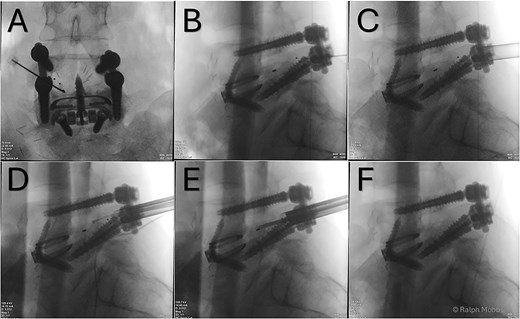

After an adequate interval recovery of 3 days, the patient underwent the second stage of minimally invasive removal of the TLIF cage via an endoscopic approach. The Elliquence Stenosis endoscopic system was used (Elliquence, USA) for TLIF retrieval. Under fluoroscopic guidance, the TLIF cage was identified with a dilator positioned directly superficial to the cage, then a 10 mm working channel positioned to insert the endoscope (Fig. 3). Dissection of the TLIF cage (Fig. 4), mobilization, and retrieval (Fig. 5) was achieved with relative ease (Video 1). Using constant irrigation through the endoscope, this assisted with both hemostasis and hydrodissection of the tissue planes around the cage to aid removal. Hemostasis was achieved, and the wound was closed in standard fashion.

(A) AP X-ray. Initial needle localization over the TLIF cage. (B) Lateral X-ray with needle positioned on posterior aspect of TLIF cage. (C) Working channel positioned immediately posterior to cage. (D) RF diathermy to dissect around cage (see Video 1). (E) Dissection around cage using multiple instruments. (F) Post removal of cage, with no TLIF device evident.